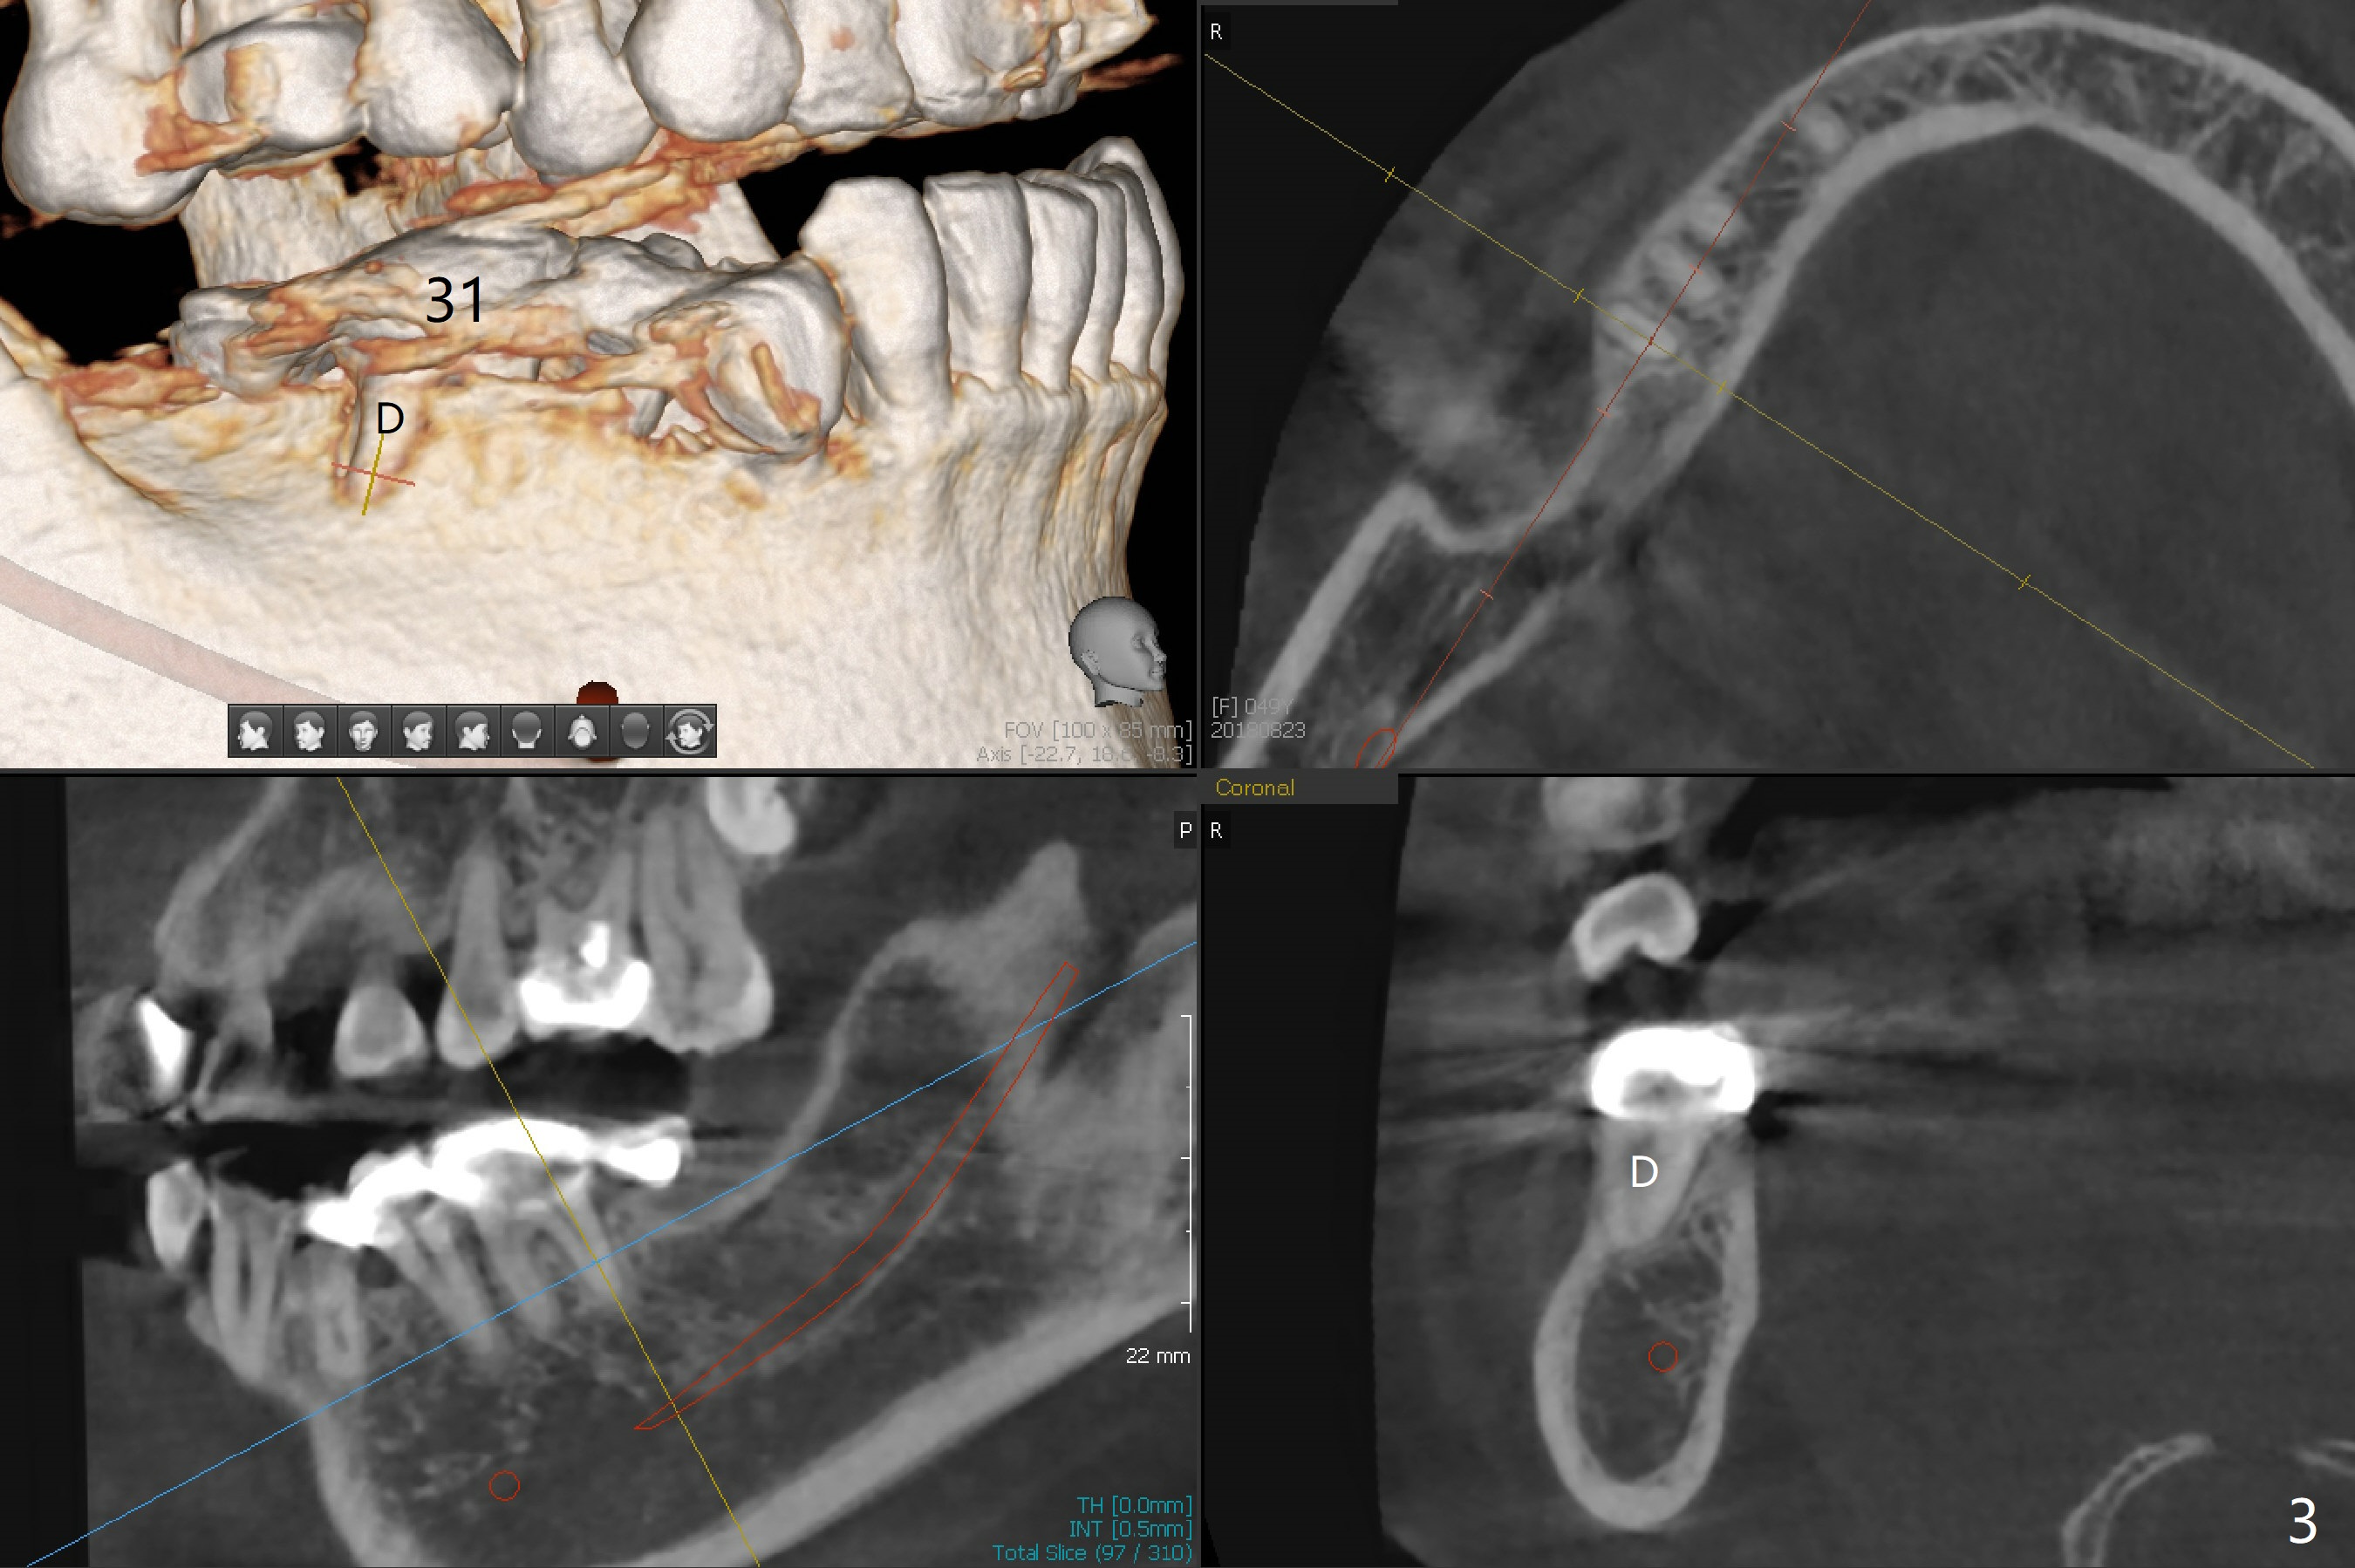

Edentulism